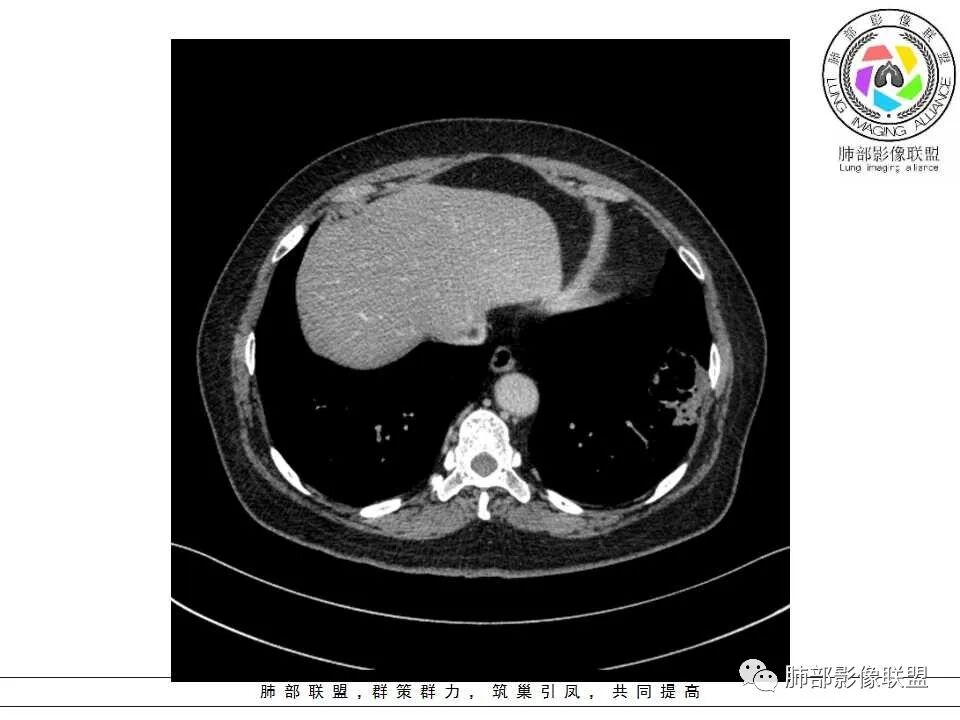

患者,女,65岁,2月余前受凉感冒后开始出现咳嗽,咳白痰,初发热2天,体温38℃左右,后降至正常,咳嗽无好转。近2日咳嗽加重,痰量增多,为黄白痰,无发热,无乏力、盗汗,无胸痛、胸闷,无头晕、头痛,无恶心、呕吐。PET-CT检查提示炎性病灶与恶性结节鉴别困难。

病灶分两部分

周围大片GGO

中央囊实性病变

南边:

病史没提咳血,周围出血灶似乎不太好说

部分边界偏清

囊腔有张力,外形有分叶,壁厚薄不均,有间隔,有强化

哪些病变可能?

1、癌

2、炎性:曲霉菌?

3、良性:囊腺瘤样畸形合并感染

1、左肺下叶外基底段不规则囊腔样病灶,囊腔内有条形影及血管穿行。

2、囊壁薄厚不均匀,稍显僵硬,有壁结节(对应边缘分叶等)、结节强化明显。

以上两条几乎将肺囊肿彻底排除在外,且高度怀疑新生物!

3、灶周环以大范围磨玻璃影,非常均匀,没有重力分布趋势,分叶状,边界隐约可变。

4、冠状位部分层面可见支气管在囊腔边缘截断。